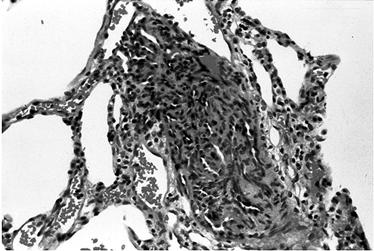

Aspect histologic arteriolar de HTP primara Leziuni plexiforme intr-un caz de HTP primara